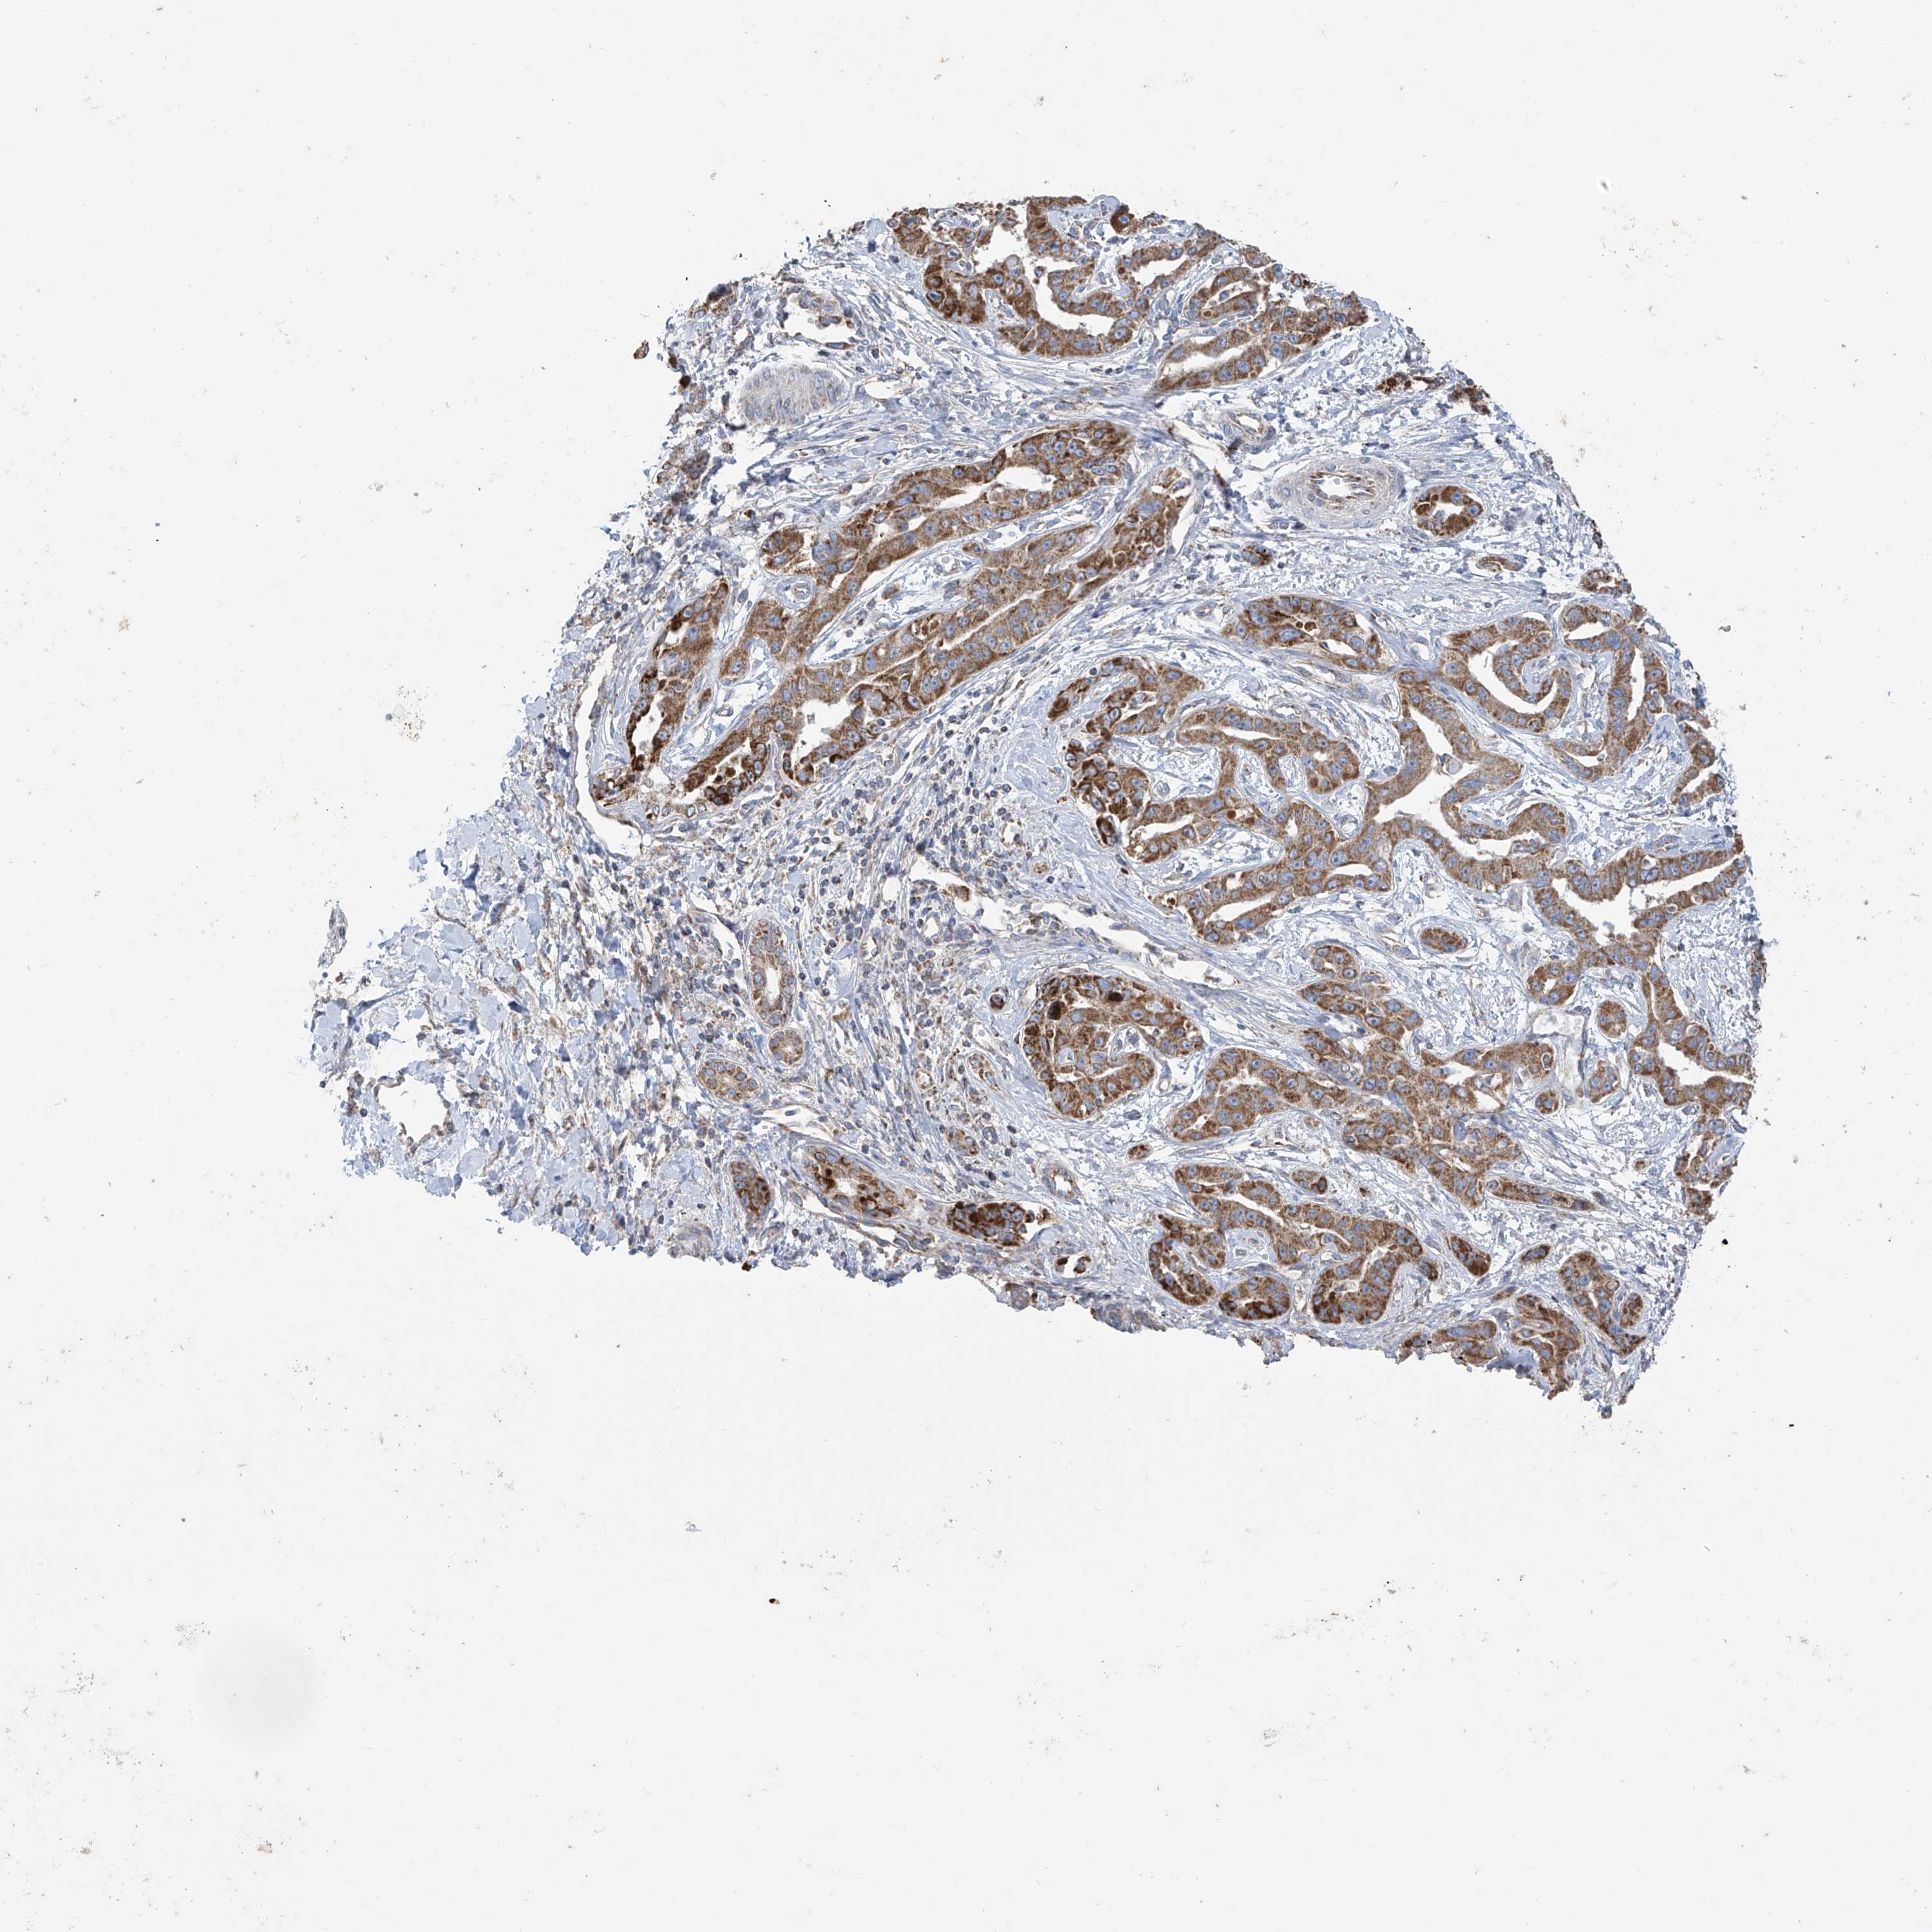

LIVER CANCER - Protein expressioni

A mouse-over function shows sample information and annotation data. Click on an image to view it in a full screen mode. Samples can be filtered based on level of antibody staining by selecting one or several of the following categories: high, medium, low and not detected. The assay and annotation is described here.

Note that samples used for immunohistochemistry by the Human Protein Atlas do not correspond to samples in the TCGA dataset.

Antibody stainingi

Antibody staining in the annotated cell types in the current human tissue is reported as not detected, low, medium, or high, based on conventional immunohistochemistry profiling in selected tissues. This score is based on the combination of the staining intensity and fraction of stained cells.

Each image is clickable and will lead to virtual microscopy that enables deeper exploration of all samples and also displays staining intensity scores, fraction scores and subcellular localization as well as patient and tissue information for each sample.

Antibody HPA034602

Antibody HPA034603

Antibody CAB033424

Staining

High

Medium

Low

Not detected

Intensity

Strong

Moderate

Weak

Negative

Quantity

>75%

75%-25%

<25%

None

Location

Nuclear

Cytoplasmic/membranous

Cytoplasmic/membranous,nuclear

Cholangiocarcinoma

Carcinoma, Hepatocellular, NOS